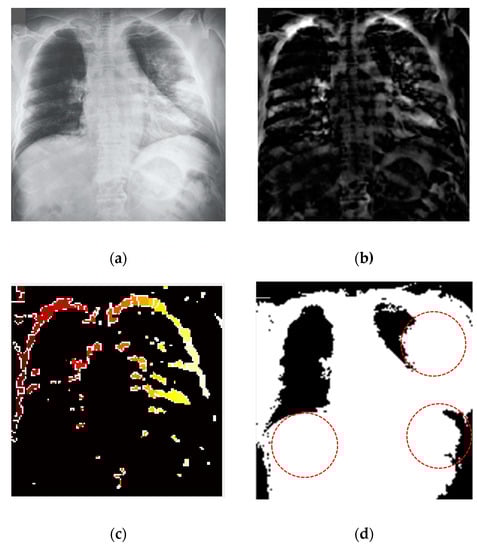

For biomedical image segmentation, the watershed technique [55] provides better results compared to the other techniques, such as Fuzzy-C means (FCM). The conventional FCM algorithm suffers from some weaknesses in terms of initializing clusters center or determining an optimal number of clusters and sensitiveness to noise [56]. FCM segmentation method cannot detect the fracture regions from the X-ray images affected by the COVID-19. However, watershed segmentation is a fast, simple and intuitive method, which provides closed contours, requires low computational time and produces a complete division of the image in separated regions. Segmentation was applied for the non-trivial task of separating the fracture lung regions from the X-ray images. A watershed segmentation technique was applied to segment the fracture regions of each image owing to its relatively less computational complexity and capability of providing high accuracy in segmentation. This method separated touching objects in an X-ray image and provided a complete division. Figure 9 presents different stages of image processing from filtering to segmentation of significant regions from the COVID-19-affected lung X-ray images.

Figure 9.

COVID-19 segmentation by using the watershed technique (a) applied anisotropic diffusion for filtering (b) adjusting the filtered image (c) watershed RBG image (d) fracture lung region caused by the coronavirus (COVID-19).